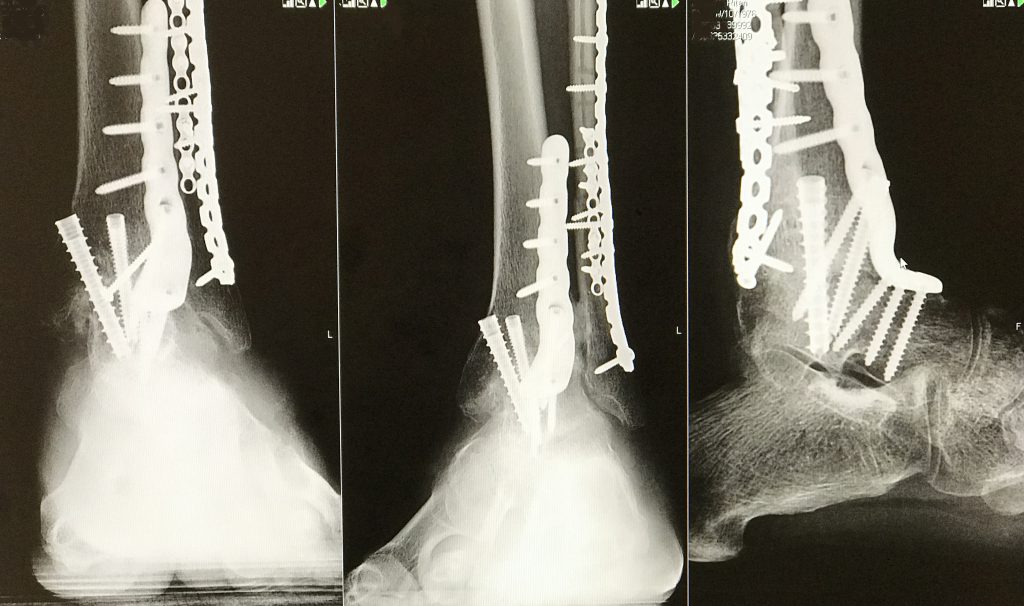

I was referred to Dr. Demetracopoulos by another physician at HSS. At our first meeting, Dr. Demetracopoulos was very interested in helping me improve my current condition. I was in extreme pain due to my ankle joint collapsing after surgery. He recommended that I have an ankle fusion, because of my age. At the time, replacement ankle joints were not a viable solution.

Dr. Demetracopoulos preformed the ankle fusion. He was concerned that the pain I was still feeling after the fusion, and physical therapy was atypical. He thought I might have a condition called Complex Regional Pain Syndrome. He then referred me to Dr. Kramskiy.